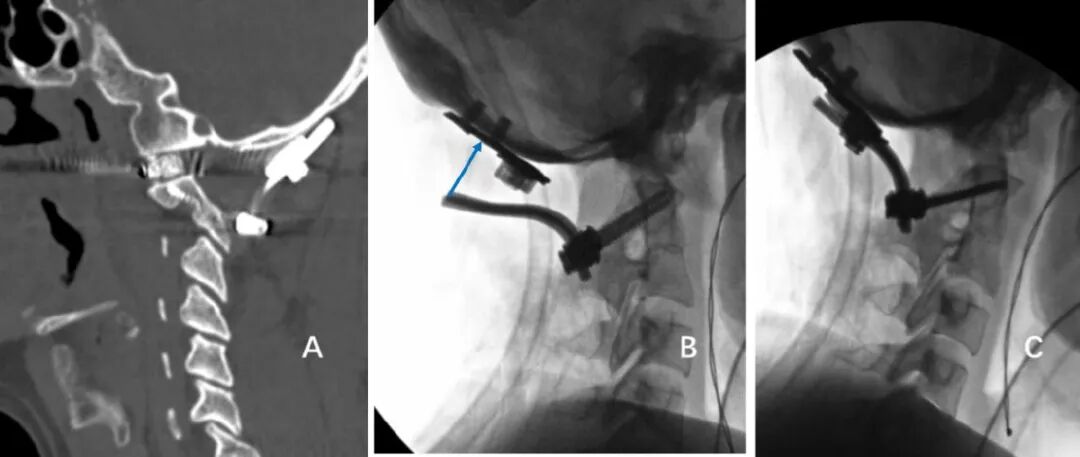

寰枢椎由3个关节构成:正中寰齿关节,两侧侧方关节。大多数寰枢椎脱位患者,特别是颅底凹陷合并的寰枢椎脱位患者,寰枢椎关节存在严重畸形,畸形的关节突发生严重的绞锁(图1),这导致寰枢椎脱位复位具有很大难度[1, 2]。

通过后路关节间撑开可以有效松解寰枢椎前方张力带,使寰枢椎侧方关节纵向分离,复位颅底凹陷和寰枢椎脱位。在寰枢椎关节间隙植入高度适宜的关节间融合器,通过融合器的支撑使寰枢椎关节纵向分离后保持稳定。而后以关节间融合器为支点,通过后路内固定系统进行悬臂操作,可以进一步复位寰枢椎水平脱位(图2)。PFDF技术大幅度提高了寰枢椎脱位后路手术的复位率,简化了寰枢椎脱位复位手术技术,降低了手术难度,提高了手术的安全性[6, 7]。

8、术中椎动脉保护

颅颈交界区骨性结构畸形常常伴有椎动脉走行异常,特别是寰枕融合畸形。当寰枕融合畸形发生时,寰椎后弓、两侧侧块、横突与枕骨融合消失,导致椎动脉V3段穿过枢椎横突孔后便失去了寰椎横突孔和寰椎后弓等骨性结构的引导,进而出现走行异常,椎动脉直接向内侧跨过枢椎椎弓峡部进入椎管。椎动脉V3段走行异常会遮挡寰枢椎关节面的后方(图8),增加了从后路在进行寰枢椎关节间操作和寰枢椎椎弓根置钉过程中损伤椎动脉的风险。

对于高风险型椎动脉,我们采用的治疗策略是将椎动脉向头侧抬起。显露寰枢椎关节后缘后,将关节间撑开器完全插入关节,如此,在旋转撑开器对关节间隙进行撑开的过程中,与椎动脉接触的是撑开器柱状的连接杆,避免对椎动脉造成卡压和切割,降低椎动脉损伤的风险(图13)。